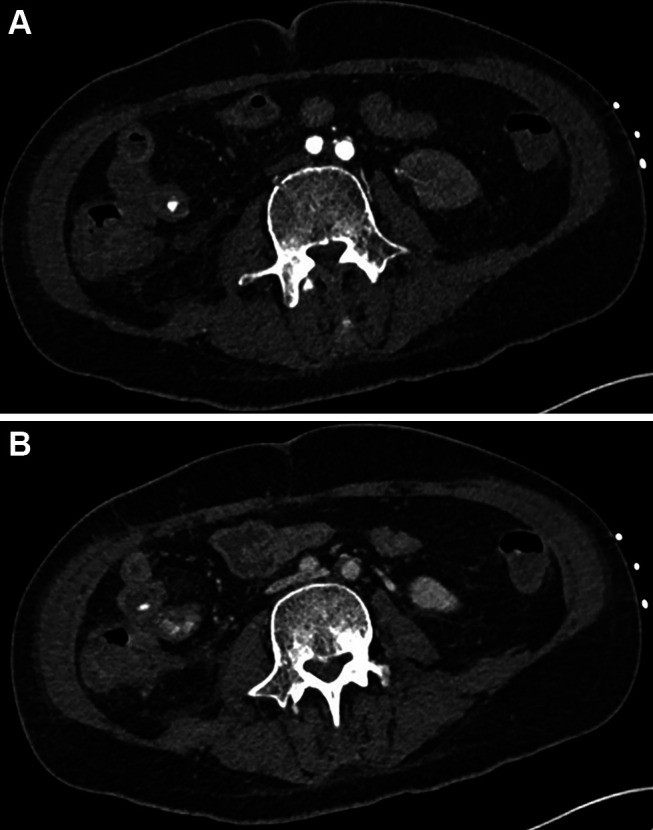

Case report: We report the case of a 44-year-old male with acute myeloid leukemia (AML) and intestinal Behçet's disease who developed severe NE during induction chemotherapy. Initial conservative management was guided by serial cross-sectional imaging, which revealed progressive bowel wall thickening, pneumatosis intestinalis, and signs of ileus. The clinical course was complicated by septic shock, multiorgan dysfunction, and later, acute gastrointestinal hemorrhage. Active arterial bleeding was identified via computed tomography angiography and successfully treated with interventional radiological coil embolization. Surgical intervention was avoided. Multidisciplinary collaboration, including hematology, radiology, rheumatology, intensive care, and pain management, was essential in navigating this complex clinical scenario.